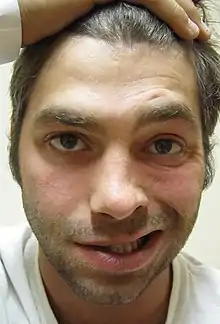

Facial expression (VII)

The facial nerve (VII) controls most muscles of facial expression, supplies the sensation of taste from the front two-thirds of the tongue, and controls the stapedius muscle.[16] Most muscles are supplied by the cortex on the opposite side of the brain; the exception is the frontalis muscle of the forehead, in which the left and the right side of the muscle both receive inputs from both sides of the brain.[16]

Damage to the facial nerve (VII) may cause facial palsy. This is where a person is unable to move the muscles on one or both sides of their face.[16] The most common cause of this is Bell's palsy, the ultimate cause of which is unknown.[16] Patients with Bell's palsy often have a drooping mouth on the affected side and often have trouble chewing because the buccinator muscle is affected.[3] The facial nerve is also the most commonly affected cranial nerve in blunt trauma.[20]

Damage to the nerve may lead to fasciculations or wasting (atrophy) of the muscles of the tongue. This will lead to weakness of tongue movement on that side. When damaged and extended, the tongue will move towards the weaker or damaged side, as shown in the image.[17] The fasciculations of the tongue are sometimes said to look like a "bag of worms". Damage to the nerve tract or nucleus will not lead to atrophy or fasciculations, but only weakness of the muscles on the same side as the damage.[17]

A cranial nerve exam starts with observation of the patient, as some cranial nerve lesions may affect the symmetry of the eyes or face.[16] Vision may be tested by examining the visual fields, or by examining the retina with an ophthalmoscope, using a process known as funduscopy. Visual field testing may be used to pin-point structural lesions in the optic nerve, or further along the visual pathways.[17] Eye movement is tested and abnormalities such as nystagmus are observed for. The sensation of the face is tested, and patients are asked to perform different facial movements, such as puffing out of the cheeks. Hearing is checked by voice and tuning forks. The patient's uvula is examined. After performing a shrug and head turn, the patient's tongue function is assessed by various tongue movements.[16]